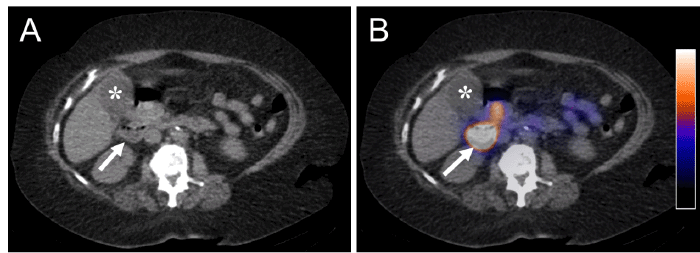

Figure 2. SPECT/CT confirms absence of radiotracer filling of the gallbladder. Published with Permission

Axial CT (A) and fused SPECT/CT (B) images of the abdomen at the level of the gallbladder demonstrate excreted radiotracer within the duodenum (white arrows) without evidence of radiotracer within the gallbladder more anteriorly (*)

Dynamic anterior planar images from HIDA scintigraphy obtained over 60 minutes immediately after intravenous radiotracer administration (5.36 mCi of 99mTc-Mebrofenin) demonstrated adequate clearance of the radiotracer from the blood pool, normal hepatic radiotracer uptake, and timely excretion of radiotracer into the common bile duct (CBD) and duodenum (Figure 1). Based on a prior CT, it was known the patient’s gallbladder was adjacent to the second portion of the duodenum, which made determining whether radiotracer was filling the gallbladder on anterior planar views challenging, even on 4-hour delayed images (Figure 1). Additional right lateral and left anterior oblique planar views were obtained but did not confirm the presence or absence of radiotracer within the gallbladder. Given the high clinical suspicion for acute cholecystitis and the patient’s desire for diagnostic certainty in order to avoid an unnecessary operation, the decision was made to obtain additional images using single-photon emission computed tomography-computed tomography (SPECT/CT). SPECT/CT utilizes the radiotracer injected as part of the HIDA scan and generates cross-sectional, rather than planar, scintigraphy images that allow for improved anatomic localization. SPECT/CT confirmed the absence of radiotracer within the gallbladder and presence of excreted radiotracer in the duodenum, concordant with the clinically-suspected diagnosis of acute cholecystitis (Figure 2).